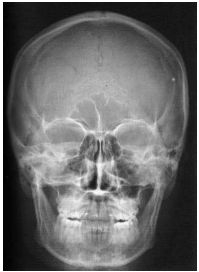

Analise as radiografias da face abaixo e marque a alternativa que contém o nome das incidências correspondentes.

01 -

02 -

A

1. Perfil 2. Mento-naso.

B

1. Mento-naso 2. Axial submento

C

1. Fronto-naso 2. Axial submento

D

1. Fronto-naso 2. Mento-naso.